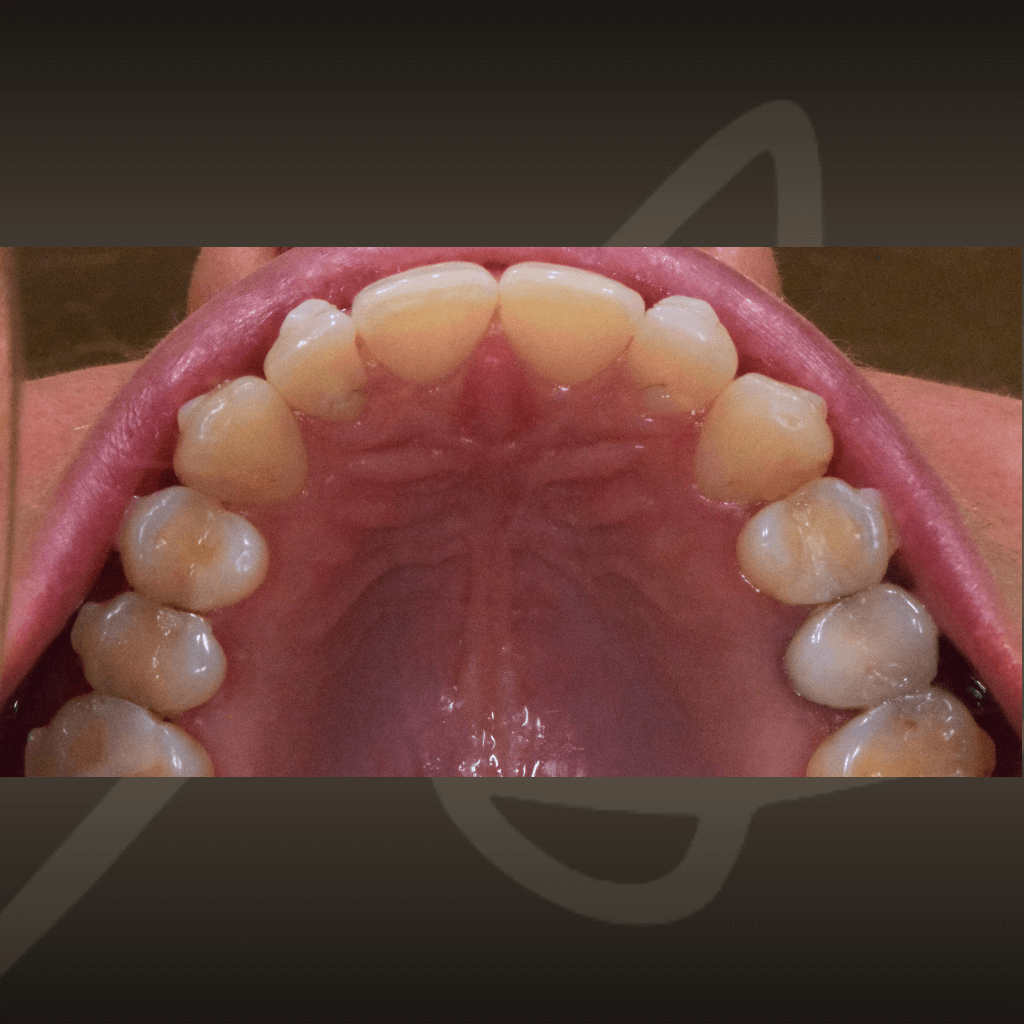

Ортодонтията не е само въпрос на подредба. Правилното лечение подобрява захапката, речта и създава стабилна основа за дългосрочно дентално здраве. Независимо от възрастта, ортодонтското лечение може да допринесе за по-добър функционален баланс и по-лесна поддръжка на зъбите във времето.